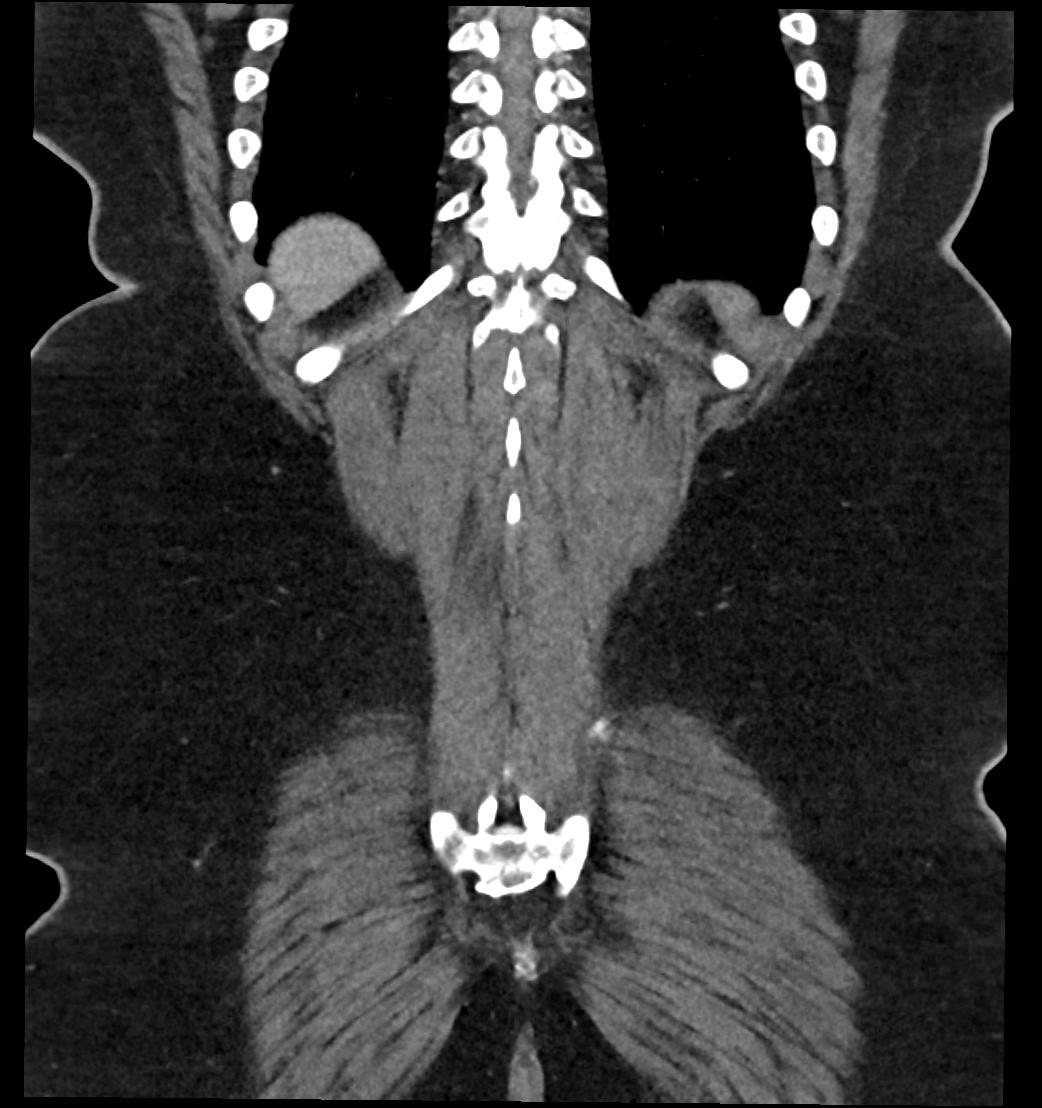

Patient: Padmakumar A. , *1988-04-24, PID: 3000069741773230809

Study Description: CT ABDOMEN

Image Series: Abdomen Cor 3mm [4]